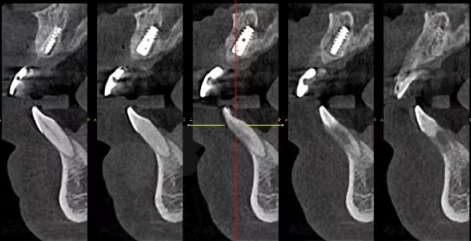

种牙齿手术通常分为几个步骤。首先是术前检查,医生会对患者的口腔进行全方面检查,包括拍摄X光片、CT等,以了解牙槽骨的情况、确定种植体的位置和方向。接着是局部麻醉,在麻醉生效后,医生会在牙槽骨上制备一个合适的种植窝,然后将种植体植入其中。之后会缝合创口,等待种植体与牙槽骨愈合,这个过程一般需要3 - 6个月。待种植体与牙槽骨达到良好的骨结合后,再进行二期手术,安装基台。末尾制作并安装牙冠,整个种牙齿手术就完成了。整个过程中,患者在局部麻醉下通常不会感到明显的疼痛,但术后可能会有一些轻微的不适。